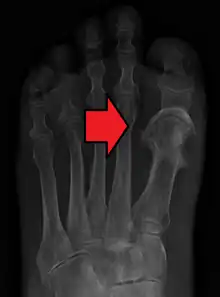

| Osteomyelitis of the 1st toe | |